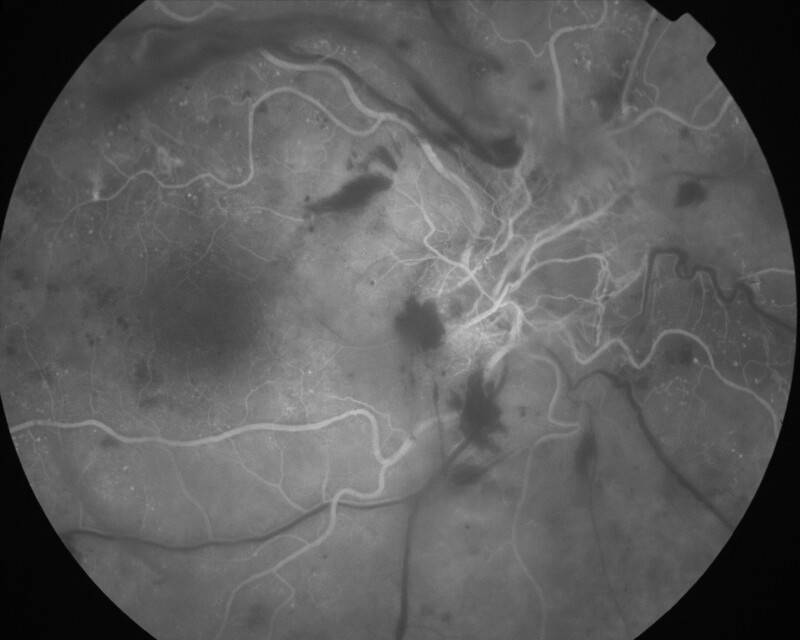

RETINOPATHIE DIABETIQUE PROLIFERANTE